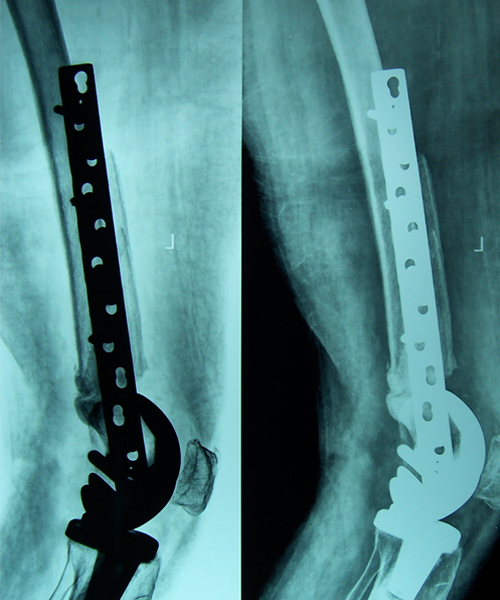

Case:1 Polytrauma Case (Multiple Fractures in Ipsilateral Limb)

Pre-Op Knee (AP & Lateral)

Post-Op Knee

4 Months Post Operative X-ray showing #s united

3 Months Follow up